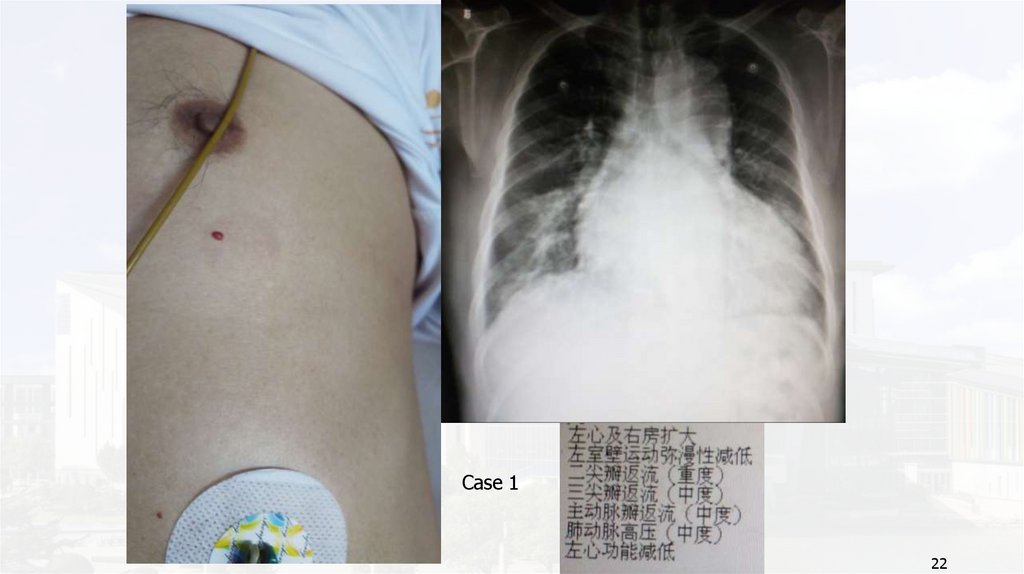

Case 1

22